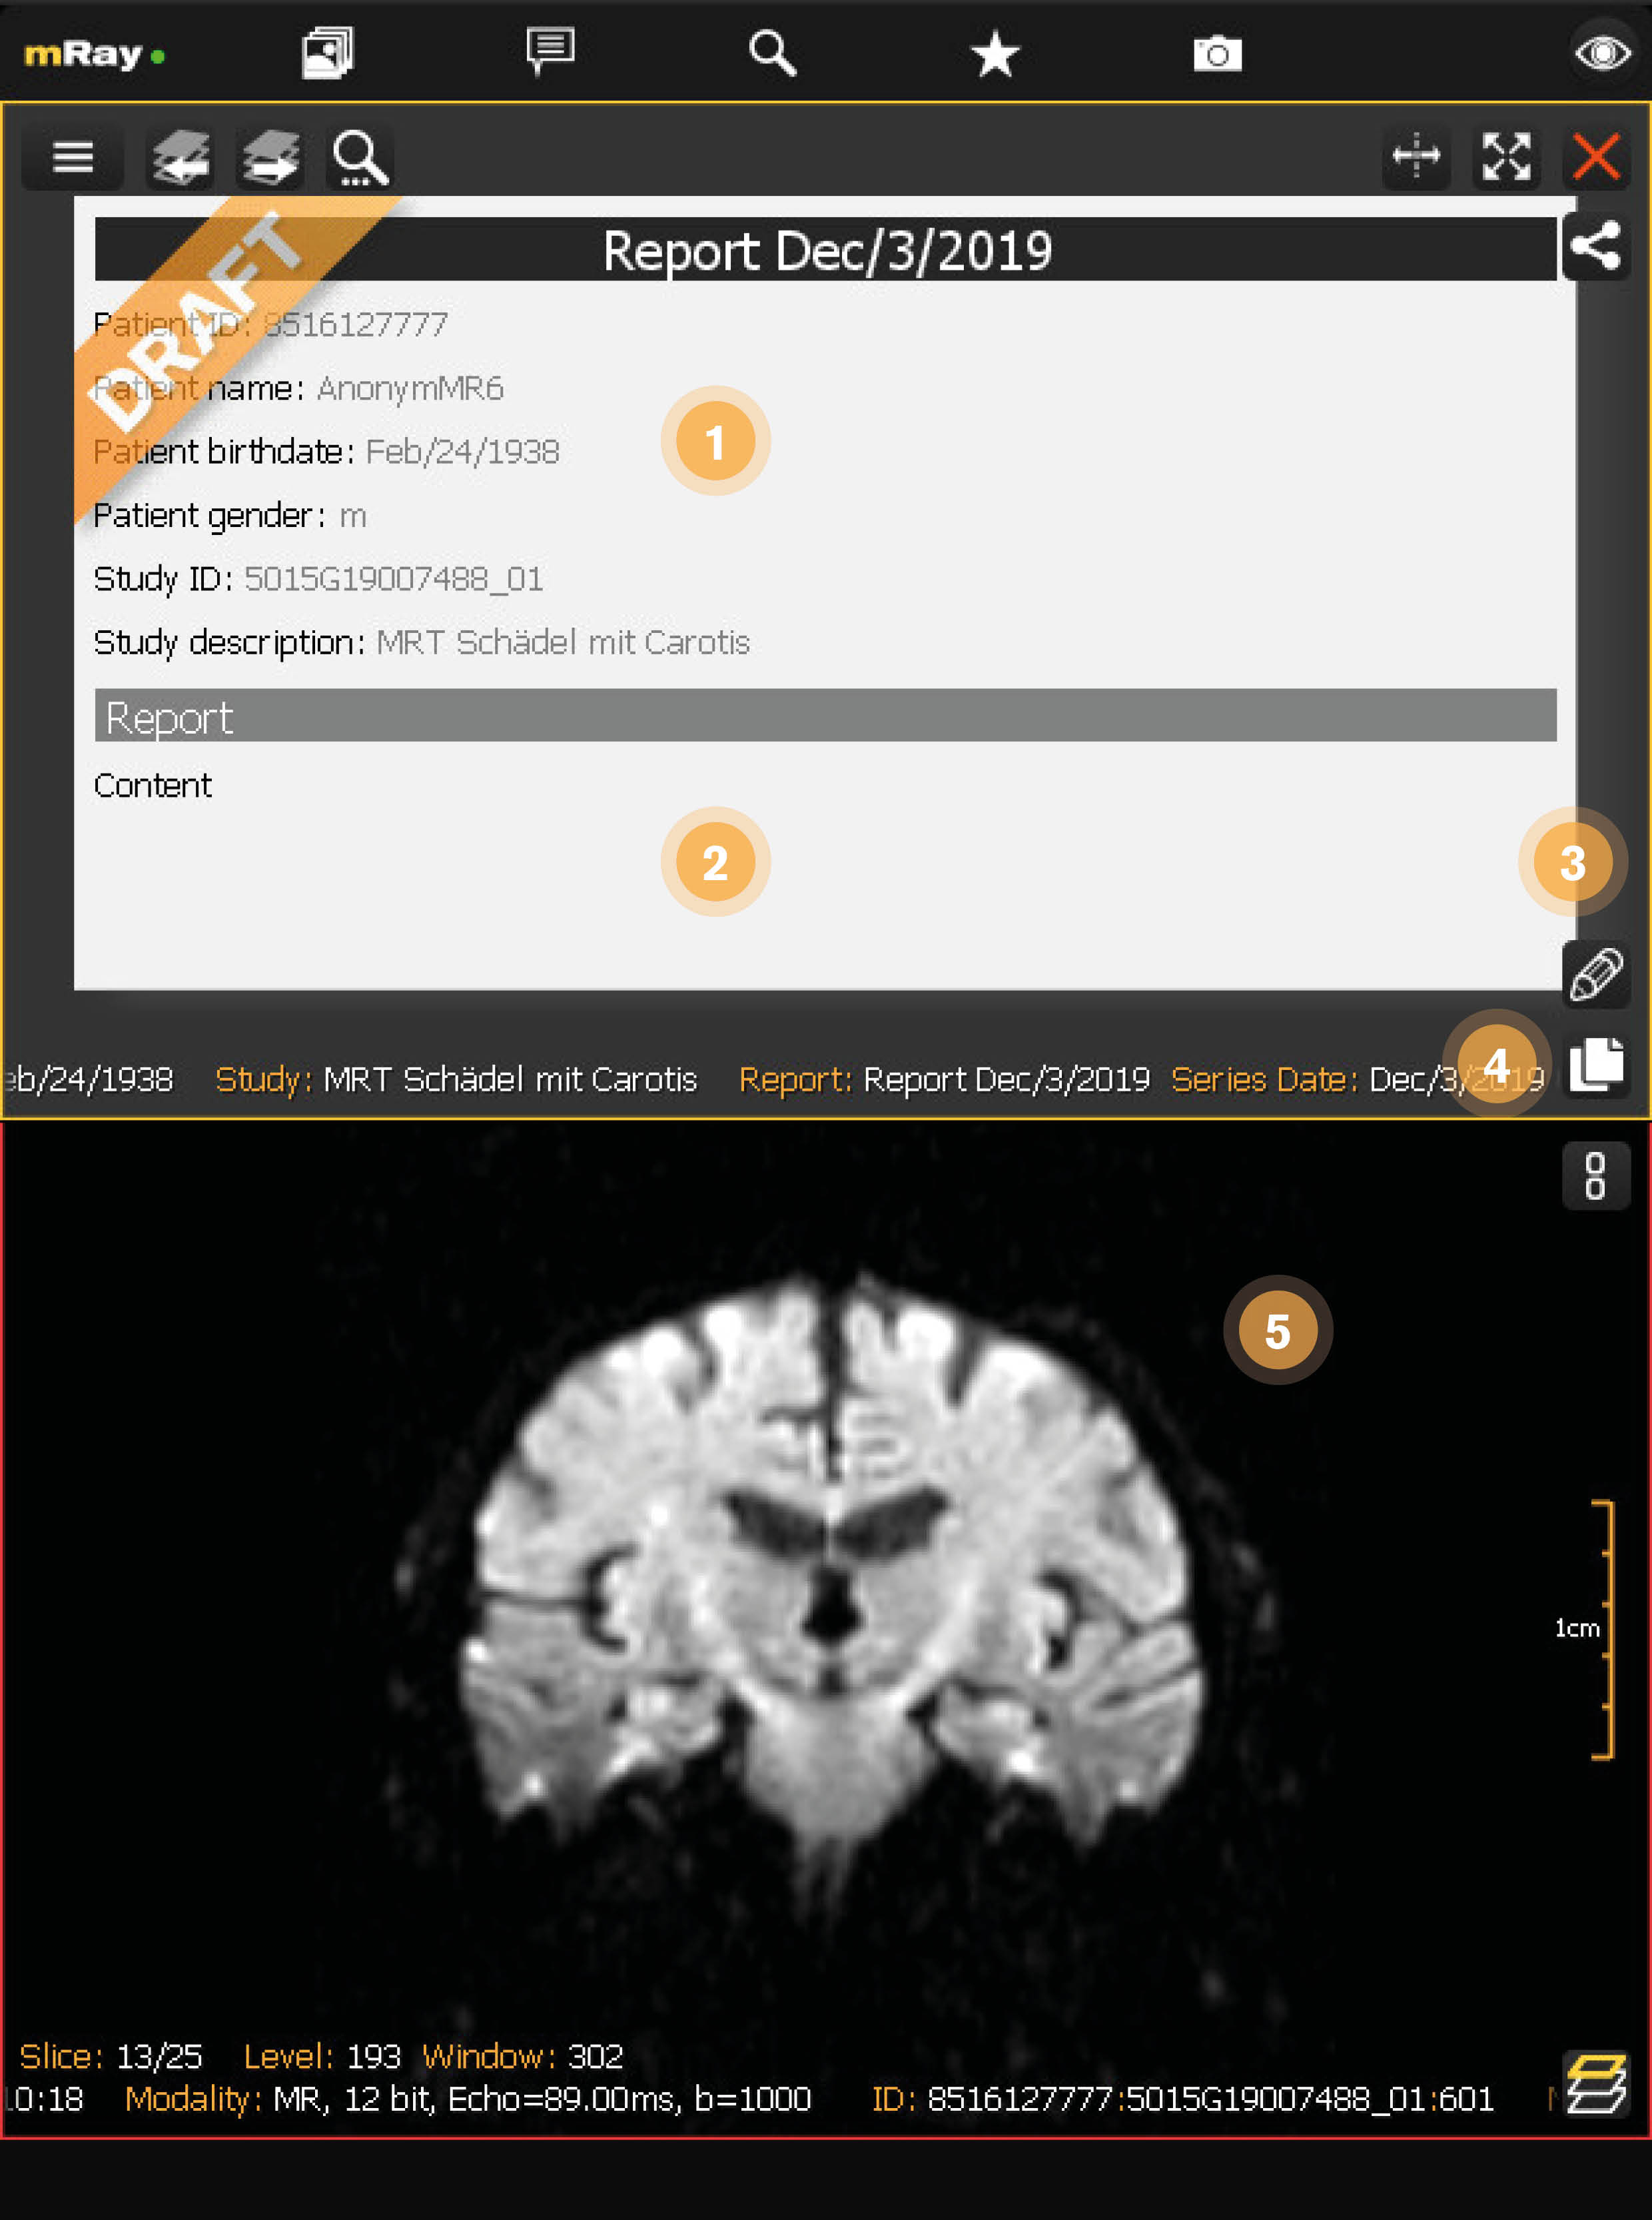

12.4. Entwurf Leseansicht

Wenn man einen Entwurf aus der Inbox öffnet, sieht man anschließend die Leseansicht. Diese Ansicht lässt sich immer öffnen, auch wenn der Entwurf von einem anderen Nutzer gesperrt ist. Die Sperrung durch einen anderen Nutzer wird anhand eines Schlosses symbolisiert.

-

Entwurf Zusammenfassung: Zeigt alle Informationen über den geöffneten Entwurf an.

-

Entwurf Inhalt: Der Text der zu dem geöffneten Entwurf hinzugefügt wurde.

-

Entwurf bearbeiten: Öffne diesen Entwurf in der Entwurf Bearbeitungsansicht.

-

Inhalt kopieren: Fügt den Inhalt des Entwurfs in die Zwischenablage ein.

-

Zugehörige Studie: Zeigt die verknüpfte Studie an.